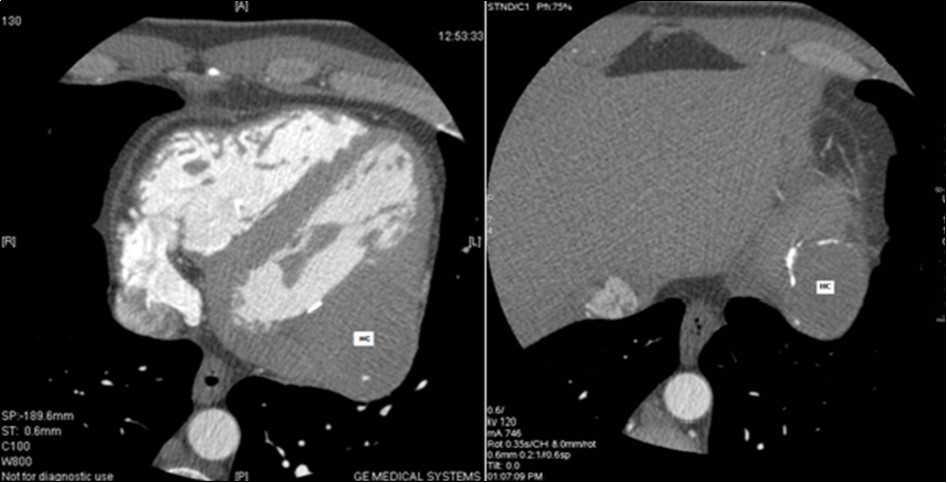

The 64-slice computed tomography (CT) showed a left ventricle intra-myocardial mass of tissue density (25 HU), not enhancing after injection of contrast, and containing multiple central and peripheral arciform calcifications (Figure 3,Figure 4,and Figure 5).

Figure 4.Coroscanner: left ventricle intra-myocardial mass of parenchymal density and calcified wall (HC: hydatid cyst).